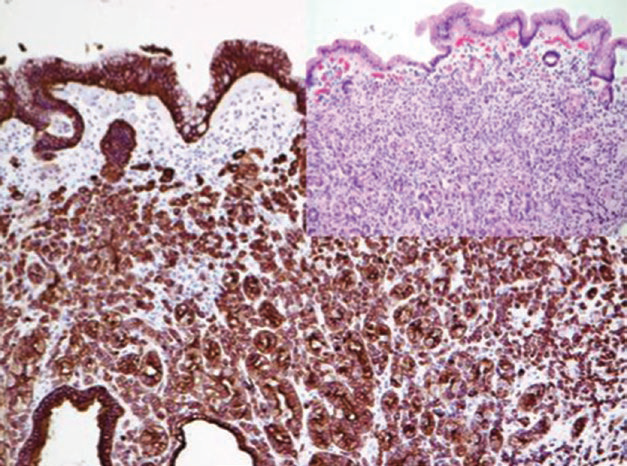

图1. 弥漫型胃腺癌中,肿瘤细胞弥漫阳性表达广谱CK(MNF116)